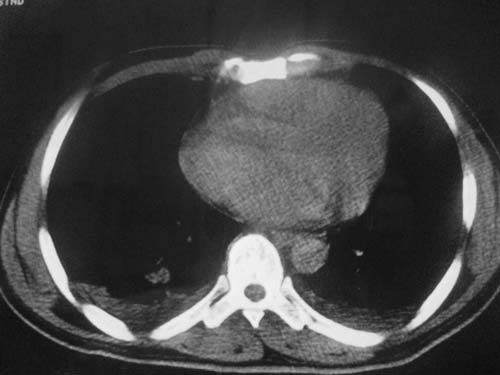

这是第三天拍的片子.